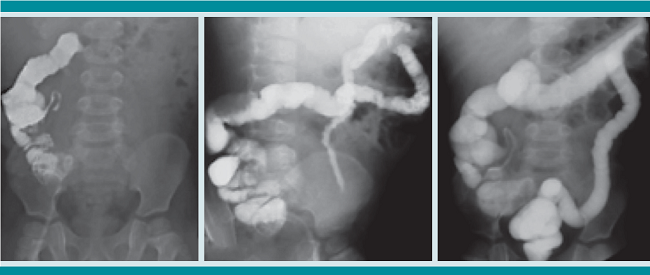

Estudio retrospectivo de serie de casos de pacientes con ileostomía tratados con la técnica de realimentación de estoma distal, previa a la restitución del tránsito intestinal, atendidos durante el año 2014. El protocolo se inició con un ileograma que descartó cualquier tipo de obstrucción mecánica desde el estoma disfuncional hasta el ano (Figura 1). En los niños con derivación, pero sin una causa de obstrucción anatómica clara, también se tomó una biopsia rectal incisional para descartar enfermedad de Hirschsprung. Después del alta hospitalaria, y en las primeras consultas posoperatorias, se inició la capacitación a los familiares en la técnica. La descripción es la siguiente: el familiar que cuida al paciente debe tomar la materia fecal de la bolsa del estoma proximal, mezclarla con 50 mililitros de solución salina al 0.9% y colar la mezcla. El líquido obtenido se introduce a través de una sonda Foley (16 French) que se coloca en el estoma distal, con el globo mínimamente inflado. Con una jeringa de 20 mL a infusión lenta, a razón de 3 mL por minuto, este procedimiento debe efectuarse tres veces al día (Figura 2). Como parte del protocolo de la realimentación se les indica que para la dilución de la fórmula láctea debe utilizarse solución salina al 0.9% y loperamida a dosis inicial de 0.5 hasta 4 mg cada 6 horas.

A todos los pacientes, previo inicio de la realimentación, se efectuó un estudio contrastado a través del estoma distal, al igual que todos los grupos que optan por la realimentación.

Debe comprobarse la permeabilidad desde el estoma hasta el ano, descartando obstrucciones y estenosis. En caso de una posible zona de transición compatible con enfermedad de Hirschsprung, también se recomienda la toma de biopsia rectal incisional.